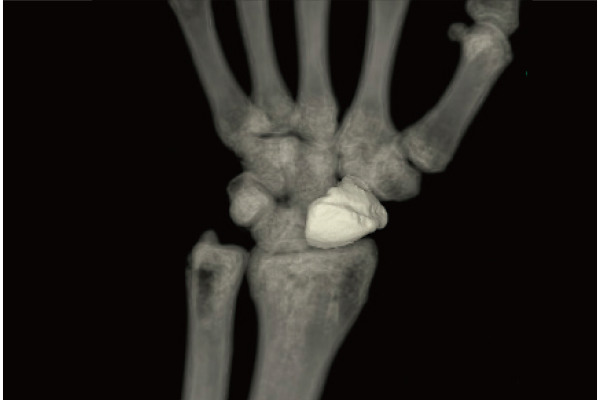

Bones are extracted or removed with one click based on the CT value and the shape of the region of interest recognized by REiLI technology.

Carpal bones removal